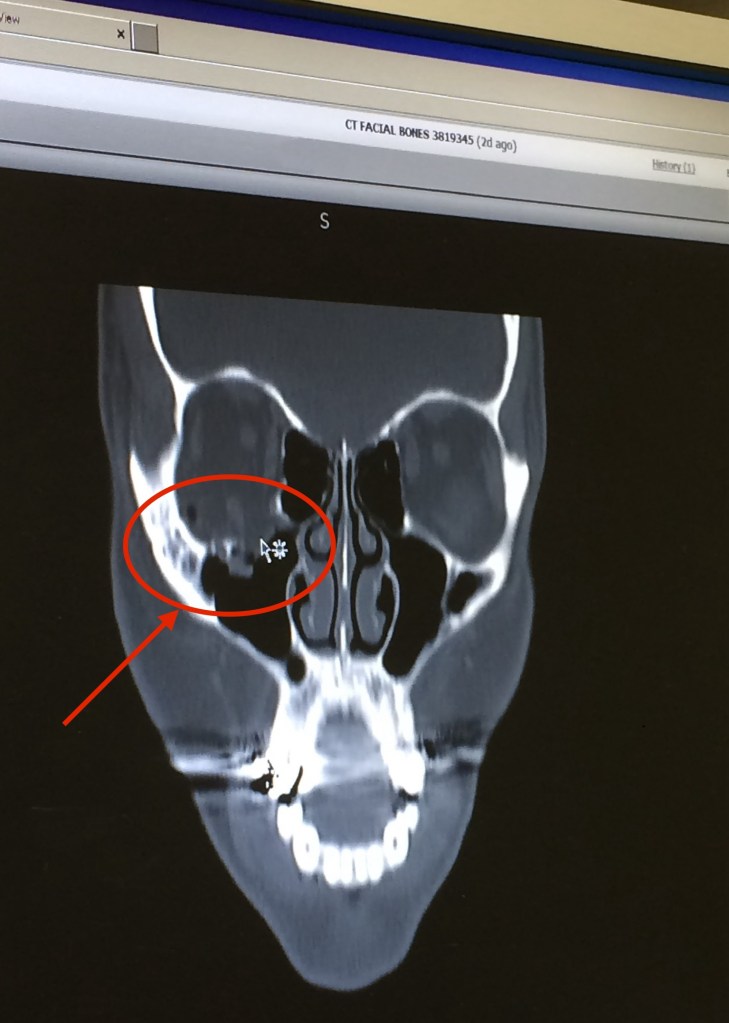

Years ago I put my faith and this scripture to the test. Around this time in 2014, I nearly lost my eye from a fall that shattered my orbital floor in my right eye. The doctors wanted me to get surgery even though I didn’t live in the area where the incident occurred. They informed me that they would need to go in, lift my eye back up and put a plate in to keep the eye stabilized. I refused the surgery because my FAITH was in my eye fully healing on its own. Sounds crazy, but I knew this situation was no match for God. Due to the incident, I no longer had right peripheral vision, was sensitive to light and my brain and eye were not communicating so basic function like walking straight and turning when someone says something to you was very limited. During that week I laid hands on my eye and prayed to God that my eye would heal on its own without surgery. I backed my prayer with Mark 16:18 “…they will lay hands on the sick , and they will recover” trusting that God’s word was true and would work on my behalf. Once I returned home, I went to an ophthalmologist to make sure my vision was still okay and my eye hadn’t dropped and everything with my vision checked out good. I’d forgotten to give my CT scans to the doctor until the end of the visit. He came back looking like he’d seen a ghost and based on the scans recommended me seeing the plastic surgeon and getting the surgery recommended by the other doctors. Again my FAITH was in my eye fully healing on its own without surgery.

Within 2 weeks my eye looked as if the injury had never happened and I had full functionality. Fast forward to my 6 month check up with the ophthalmologist, my eye had fully healed on its own with no changes to my vision and without any surgery! The doctor’s assistant came in and said “You know you’re really lucky because someone came in with the same issue and had to lose their eye. I told her “that’s not luck, that’s God! I could’ve literally lost my eye and according to the doctors the vision in the other eye would’ve diminished too…But God! He performed not just a miracle but a medically documented miracle for me! How, you ask? Because of my Faith. While faith sometimes doesn’t make sense, it does in fact make miracles.